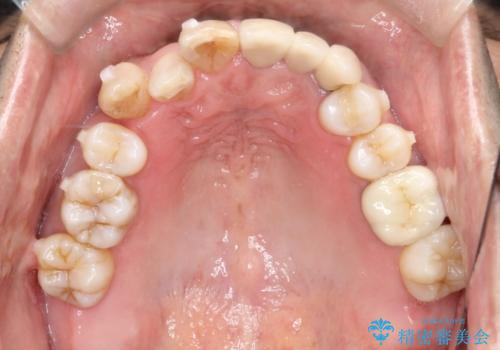

- 50代の患者様で、右上の八重歯と歯並びの乱れを気にされてご来院されました。特に、すでに装着されている前歯のセラミックブリッジを外したくないという強いご希望がありました。精密な検査の結果、八重歯を治すためのスペースが不足しているため、右上の4番目の歯(小臼歯)を抜歯し、そのスペースを利用して歯並び全体を整える治療計画を立案。装置には目立たないインビザラインを採用し、ブリッジを温存しながら八重歯の改善を目指しました。

今回の治療で最も重要だったのは、患者様のご要望通り既存のセラミックブリッジを外さずに矯正を進める点でした。計画通り右上の小臼歯を抜歯し、透明なインビザラインを使用して抜歯スペースを閉じながら、八重歯を正しい位置へ移動させました。ブリッジの形態と調和するに、他の歯の移動を工夫をすることで、複雑な条件をクリア。治療の結果、長年気にされていた八重歯が解消され、見た目が大きく改善しました。50代からでも、ご自身の要望を叶えながら、美しく機能的な歯並びを獲得していただけました。